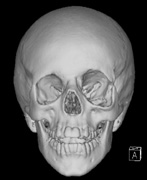

Growth of a plexiform neuroma may be directed posteriorly, infiltrating orbital tissues and involving the bony walls. Congenital plexiform neuromas of the orbit are often associated with absence of the sphenoid wing (Fig. 5). Intracranial pulsation can be transmitted to the orbit causing pulsatile proptosis or enophthalmos.57–59 Plexiform neuromas of the lid and orbit are difficult to treat; complete excision is difficult and potentially disfiguring. The tumors are vascular and may bleed copiously at surgery. They are not radiosensitive and there is also risk of inducing malignant transformation. Trials with antiangiogenic chemotherapeutic agents (thalidomide, interferon alpha) and mitotic-signaling pathway blockers (inhibition of Ras by Farnesyl protein tranferase inhibitor) are in progress.60,61

Fig. 5. Surveillance images from a 15-year-old boy with a history of visual loss, proptosis and a diagnosis of NF1. Postcontrast axial (a) and sagittal (b) T1-weighted images demonstrate a plexiform neurofibroma of the left upper and lower eyelids, which extends into the orbit and to the extraconal soft tissues through a widened superior orbital foramen, best seen in (c). An optic nerve glioma widens the optic canal. (d) A sphenoid wing dysplasia is visible and seen as asymmetry of the orbits on the 3D CT bone reconstruction images.

5. Optic glioma (Fig. 5)

6. A “distinctive” bone lesion: sphenoid bone dysplasia or thinning of long bone cortex (with or without pseudoarthrosis)